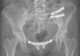

Idiopathic pubic fusion